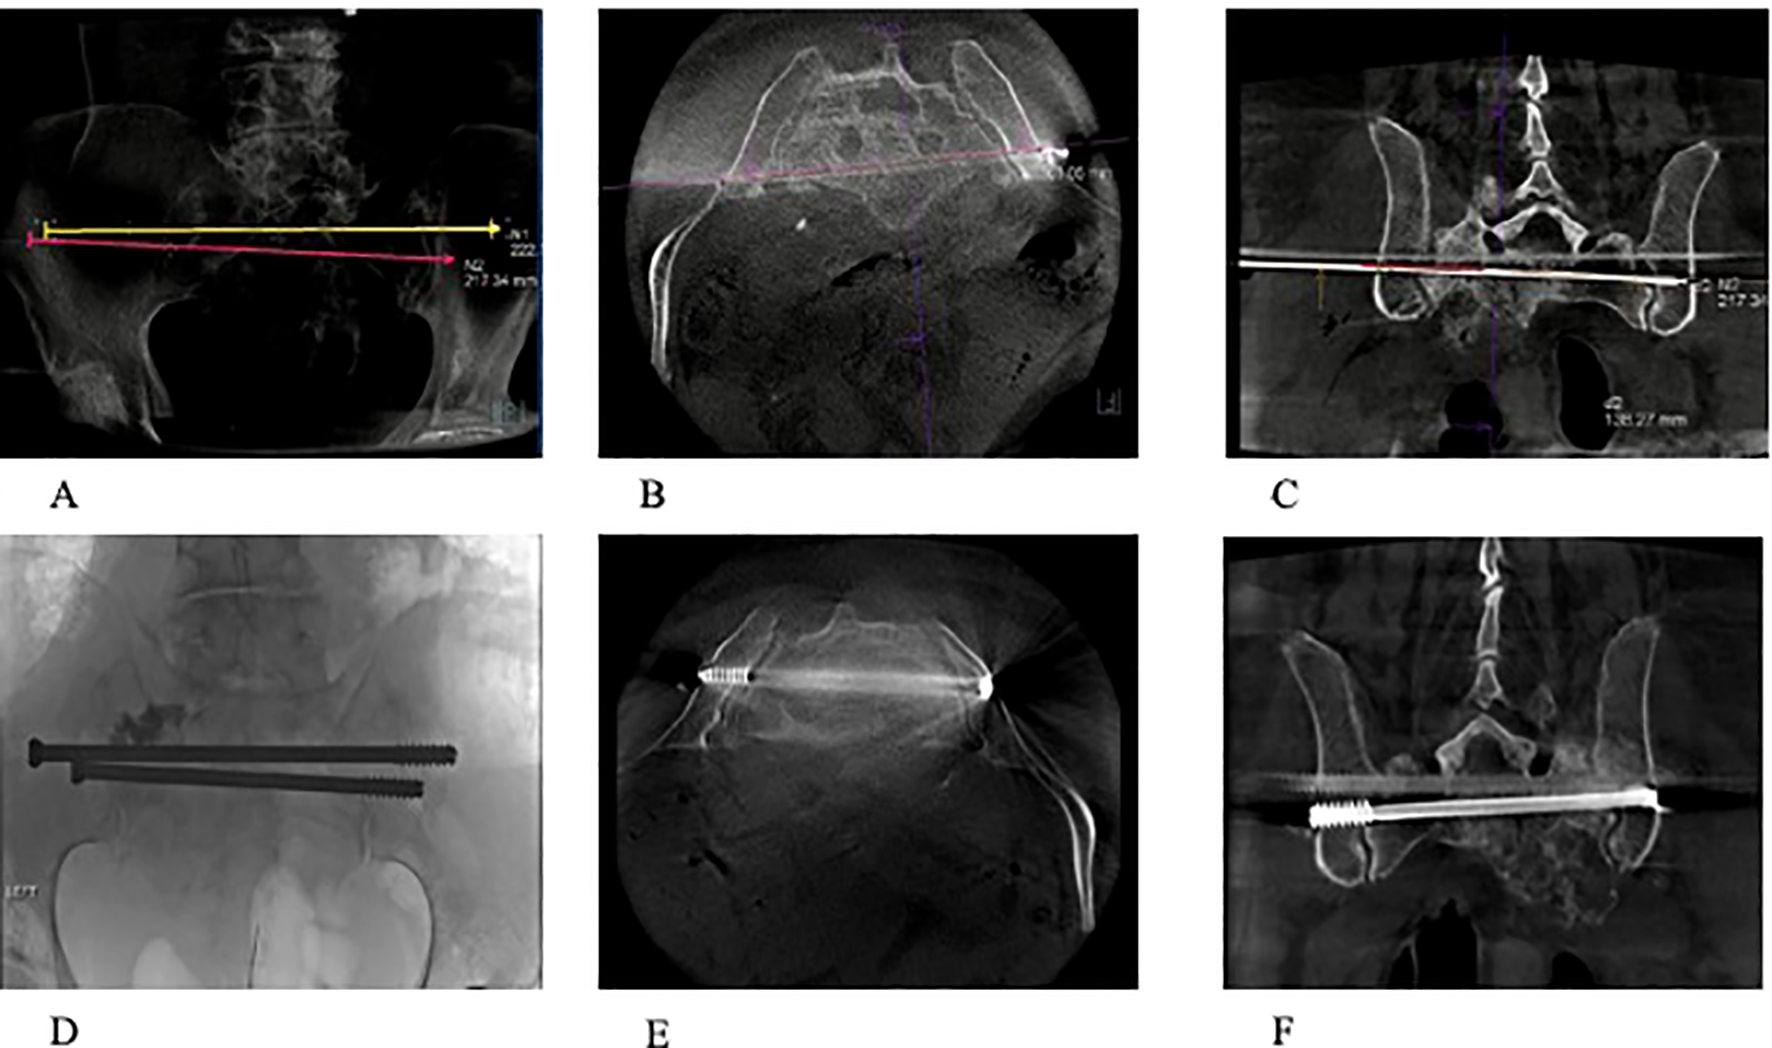

Figure 2

(A) Fluoroscopic view of 2 3.2mm guide pins passing through S1 and S2 corridors. (B) Fluoroscopic view of 8 mm cannulated screws passed through S1 and S2 corridors. (C) Fluoroscopic image during PMMA injection with 2 11-guage cannulas into weakened portions of the ilium and reinforcing entrance and anchoring positions of S1 and S2 trans-sacral screws.

Figure 3

(A–F) A 74-year-old patient with osteoradionecrosis of pathological fracture secondary to metastatic pancreatic cancer. (A–C) Radiograph and CT scans (axial and coronal) showing the planned screw trajectories through S1 and S2 corridors. (D–F) Completion radiograph and CT scans (axial and coronal) demonstrating stabilization of the sacrum with the use of percutaneous trans-sacral screw fixation and sacroplasty.

Initial CT images are obtained and then CT fluoro is used. Using angulation of the C-Arm, fluoroscopic images with augmented fluoroscopy needle guidance overlay were utilized to guide pins through sacral corridors. A cone beam CT was then performed to confirm appropriate placement of sacral guide pins without encroachment on the neural foramina. Fully threaded cannulated screws were then placed through S1 and S2 corridors. Either 8-mm or 6.5-mm (Stryker) or 7.3-mm (DePuy Synthes) cannulated screws were used (Figure 2). For each patient, the location, screw type (Ilio-sacral versus trans-sacral), and number of screws was decided based on achieving optimal fixation for improved stabilization, allowing for improved functional outcomes (Figure 3). Using fluoroscopic needle guidance, 11-gauge cannulas are either placed using the posterior to anterior approach, or trans-sacroiliac approach. Under CT fluoroscopic guidance, Polymethylmethacrylate (PMMA) cement was then injected under CT fluoroscopic guidance filling the lesion and augmenting screw fixation (Figure 2). Real-time fluoroscopy with overlaying 3-dimensional CT imaging provides superior visualization of the neuroforamina, which ensures good cement deposition and with minimal extravasation. When necessary, additional trocars were used to maximize cement filling of osseous defects and ensure screws were “potted” into the cement. Final CT images were taken prior to closure (Figure 4).